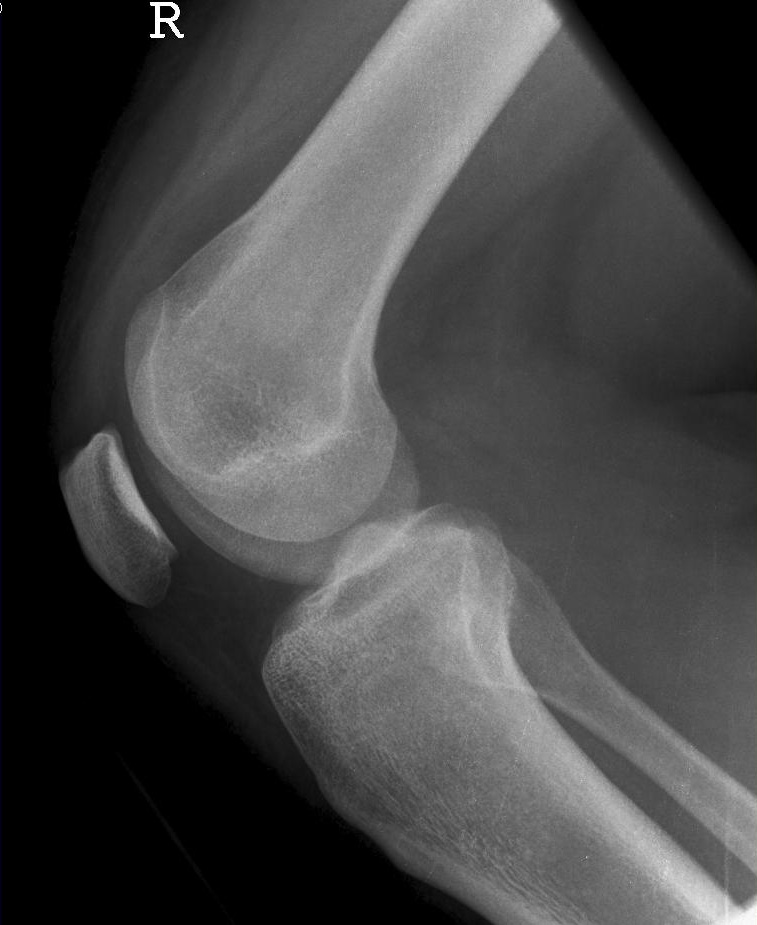

Knie seitlich

126_3.jpg

Fehler

Die Femurkondylen stehen nicht senkrecht übereinander. Zudem wird die Patella vom lateralen Anteil der Femur und das Fibularköpfchen vom Tibiakopf überdeckt.

Abhilfe

Abhilfe bringt eine weitere Drehung des Patienten nach vorne in Richtung Patella, damit die Kondylen wieder übereinander liegen.